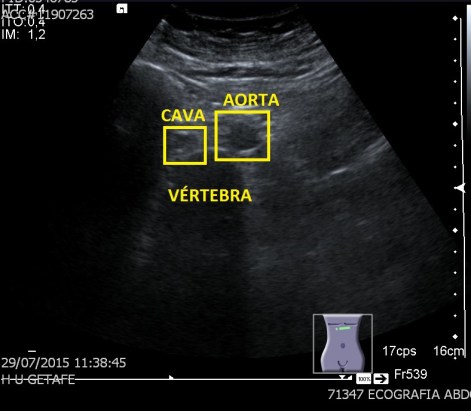

finalmente usamos una aplicación ya estudiada en el blog, como es la Panoramic View, donde podemos darle una visión global a la radióloga, donde podemos llegar a alcanzar medidas de estudio de 15 centímetros, como en este caso, cuando la medida de la huella de la sonda no supera los 5 centímetros. Visualmente es una imagen muy plástica, que ofrece a la radióloga una información no sólo de la lesión, sino también de la relación anatómica de la ecoestructura patológica con el tejido adyacente, ya sea normal o patológico.

En este caso en una misma imagen tenemos dos ecoestructuras patológicas, la masa o el tumor y la lesión vascular de los vasos, también con ecoarquitecturas normales como la del testículo anteriormente explicado.

Esta imagen es muy bonita por que puedes ver como el canal inguinal se abre para albergar a la masa, en el cordón y como a continuación el varicocele.